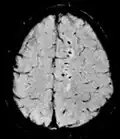

| Effective T2 or "T2-star" |

T2* | Spoiled gradient recalled echo (GRE) with a long echo time and small flip angle[74] | Low signal from hemosiderin deposits (pictured) and hemorrhages.[74] |

| |